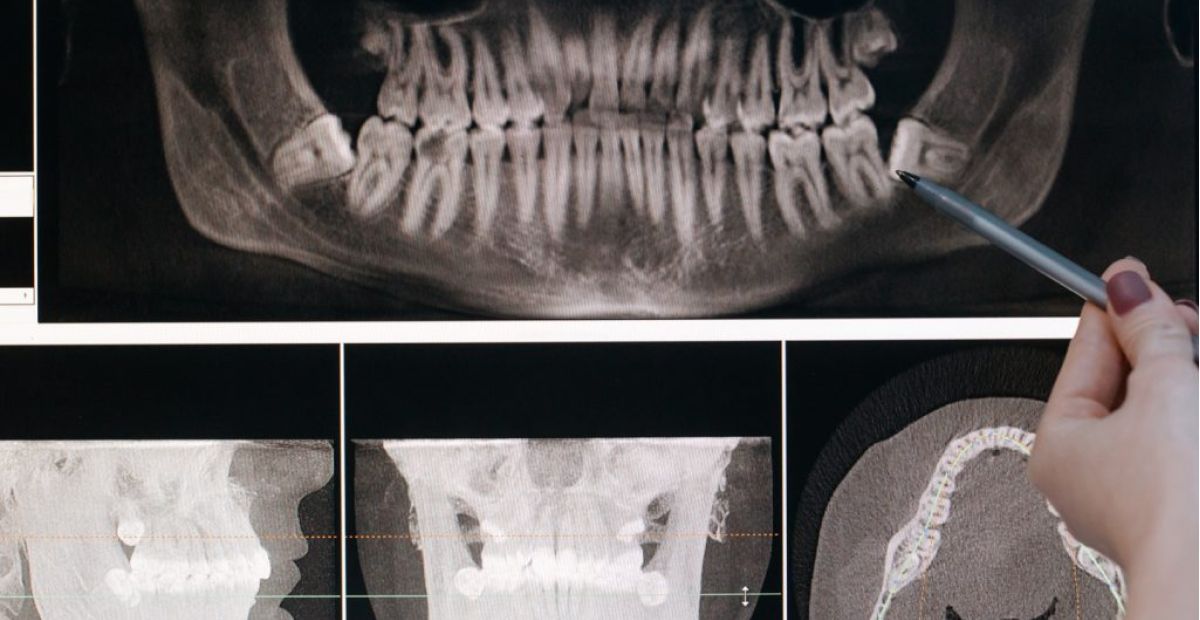

Les proves són realitzades a petició de la Fiscalia. Aquestes consisteixen en un examen de maduració òssia i dental que inclou radiografies del canell, ortopantomografies dentals i tomografies de la clavícula.

La comunitat científica internacional i els instituts de medicina legal adverteixen que aquestes tècniques presenten marges d’error significatius. En aquest sentit, les proves no tenen en compte factors ètnics o socioeconòmics que alteren el desenvolupament físic. Alhora, el mateix Departament de Salut reconeix en els seus informes que «cap d’aquests mètodes és òptim ni infal·lible».